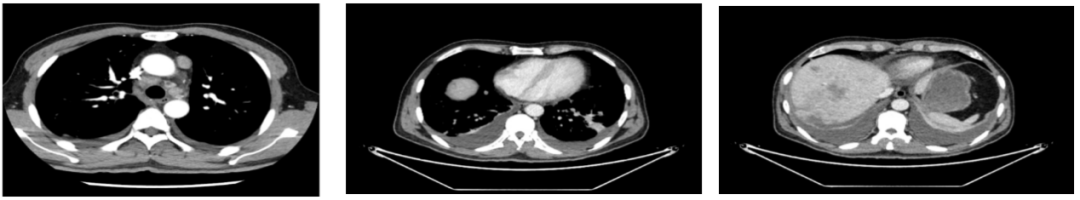

外院CT检查提示:1、两肺多发斑片状、结节影,性质待定,转移瘤?2、纵隔内多发肿大淋巴结;3、肝实质多发稍低密度影,性质待定(转移瘤可能性大)

2018-03-08 PET/CT示:胃癌(?)并全身多发淋巴结转移、肝脏多发转移、双肺上叶多发转移;

2018-11-14 CT(8周期化疗后):PD?

增强CT示:肝硬化

肝异常强化灶

胃癌并肝转移化疗后,肝内转移灶大致同期;

慢性肝病,脾大、门脉高压(食管下段-胃底静脉曲张);

双肾小囊肿;

右肺中叶外侧段、左肺上叶下舌段及右肺下叶后基底段慢性炎症;

右肺上叶前段实性微小结节,炎性结节?建议定期复查;

纵隔淋巴结转移瘤,复查大致同前。